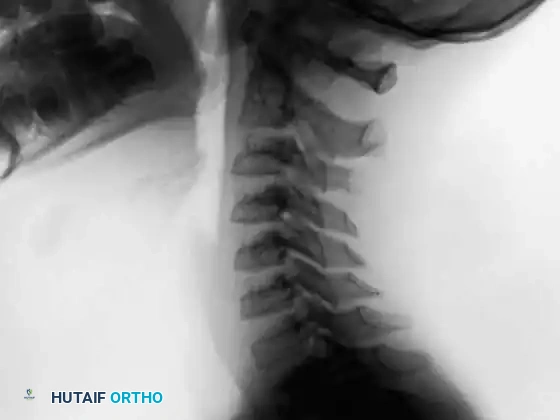

Axial and sagittal CT scans clearly defining the expansile, mineralized matrix of the osteoblastoma within the posterior elements, allowing for precise surgical planning.